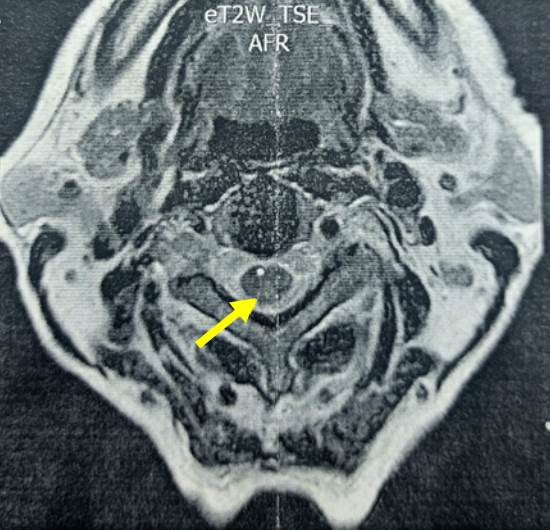

En los resultados de la RM con contraste de columna cervical y dorsal se apreciaron hiperintensidades en la región posterior de la médula espinal desde la C1 hasta T1 (figura 3), en el contexto de una mielopatía de los cordones posteriores.